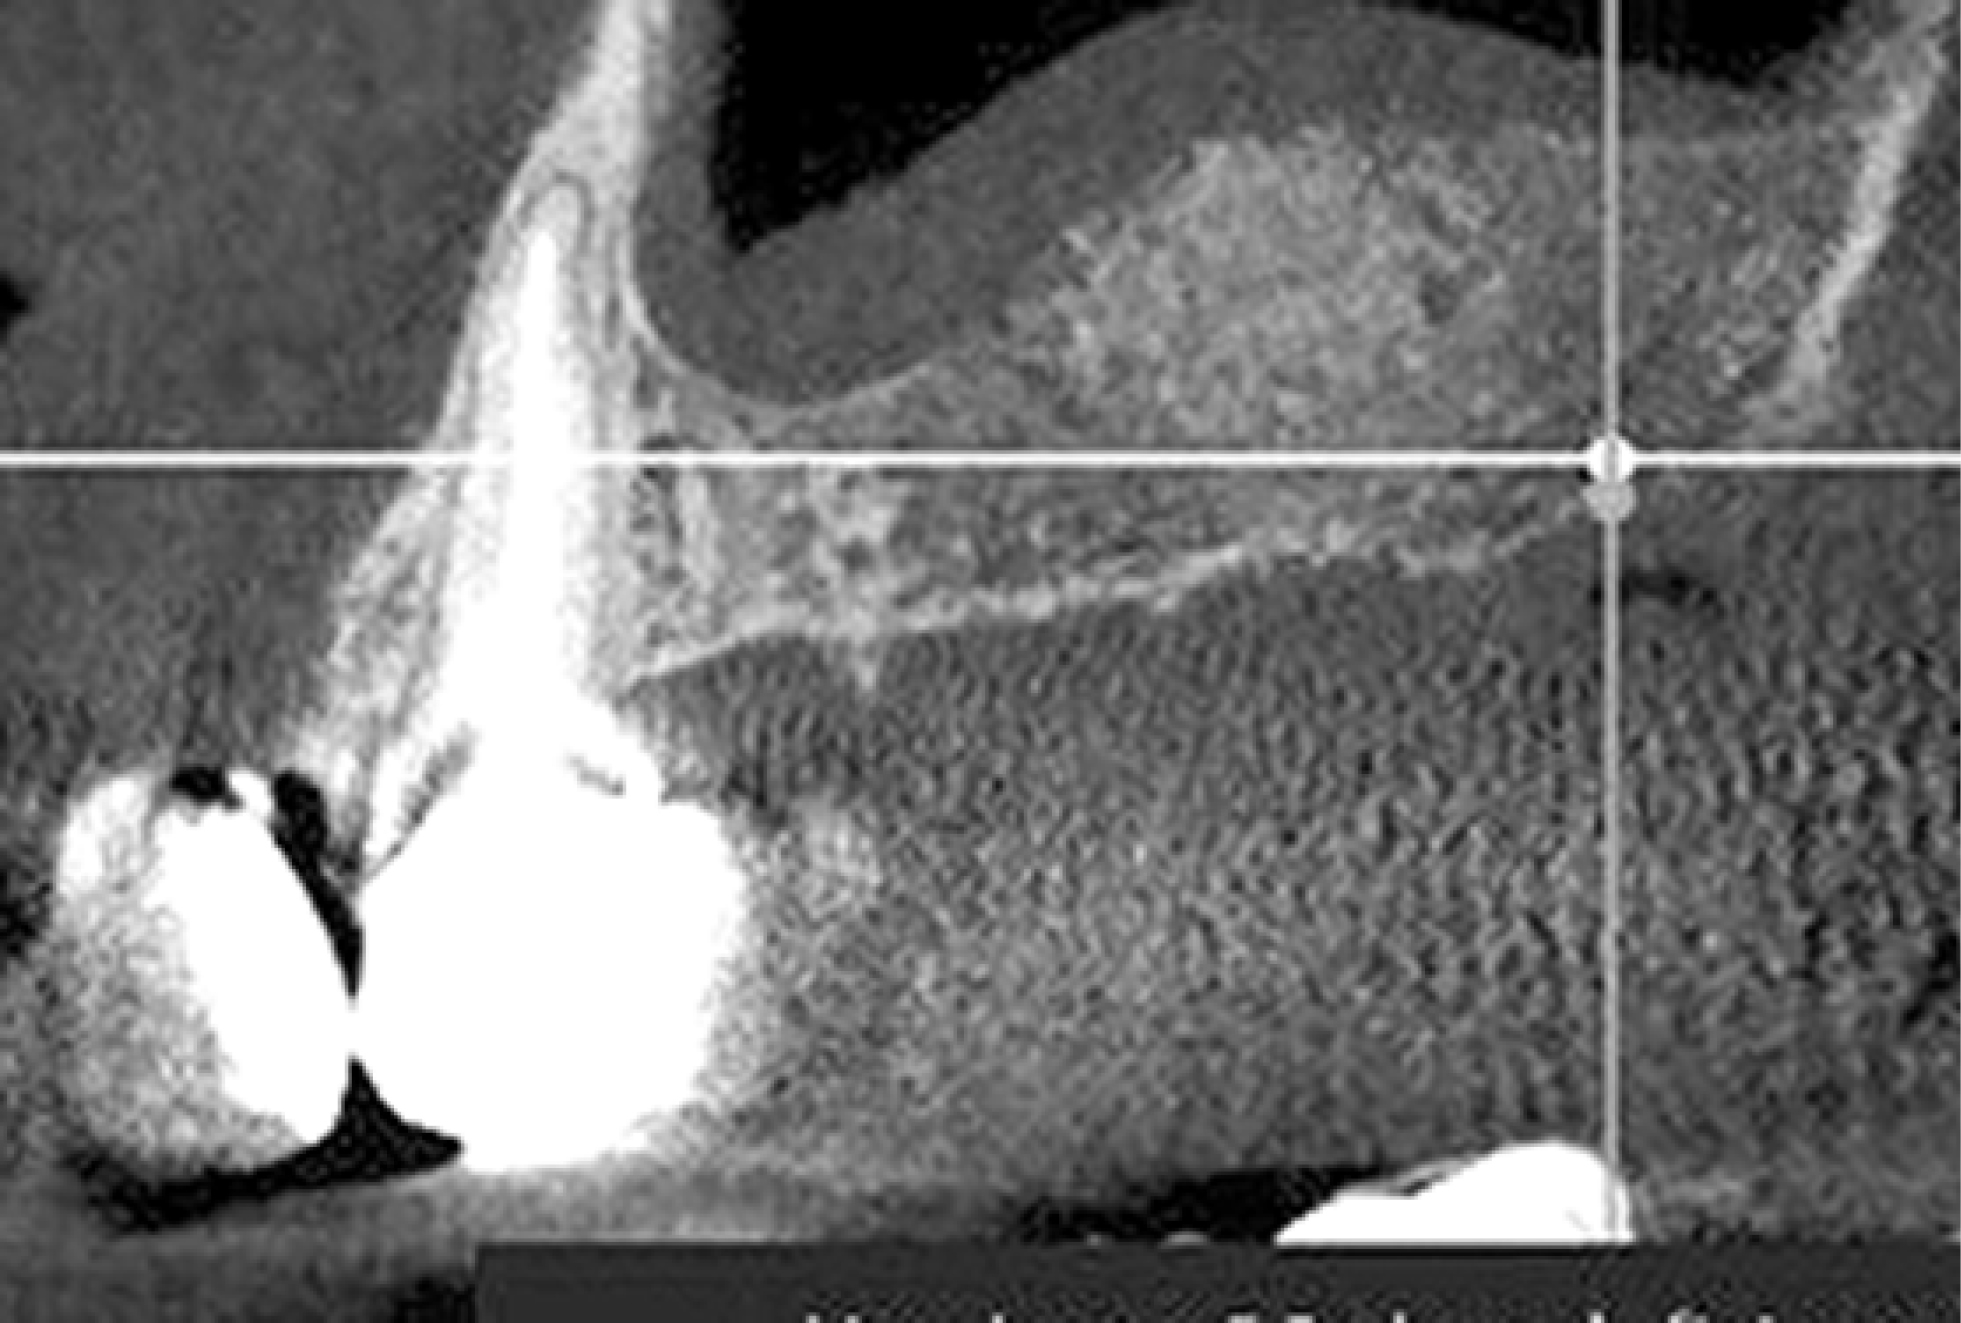

В 3-й группе использовали комбинацию материалов bioOST, bioPLATE («Кардиоплант», Россия). По данным КЛКТ визуализируется плотный участок новообразованной кости в области оперативного вмешательства (рис. 5).

Рис. 5. Сагиттальная плоскость области костной пластики материалами bioOST, bioPLATE спустя 5 мес. Конусно-лучевая компьютерная томография